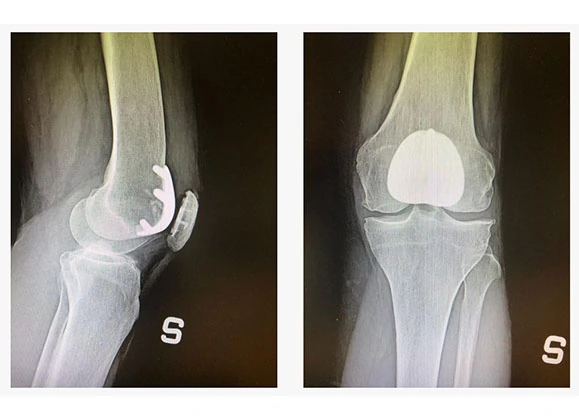

Quando l’artrosi è in fase avanzata e ha già provocato deformazioni evidenti dell’articolazione o una perdita di stabilità, l’intervento di protesi rimane l’opzione più efficace. In questi casi, la chirurgia permette di ridurre in modo significativo il dolore e di ripristinare un’articolazione stabile, consentendo alla persona di tornare a muoversi con maggiore indipendenza e senza il timore di cedimenti o cadute.